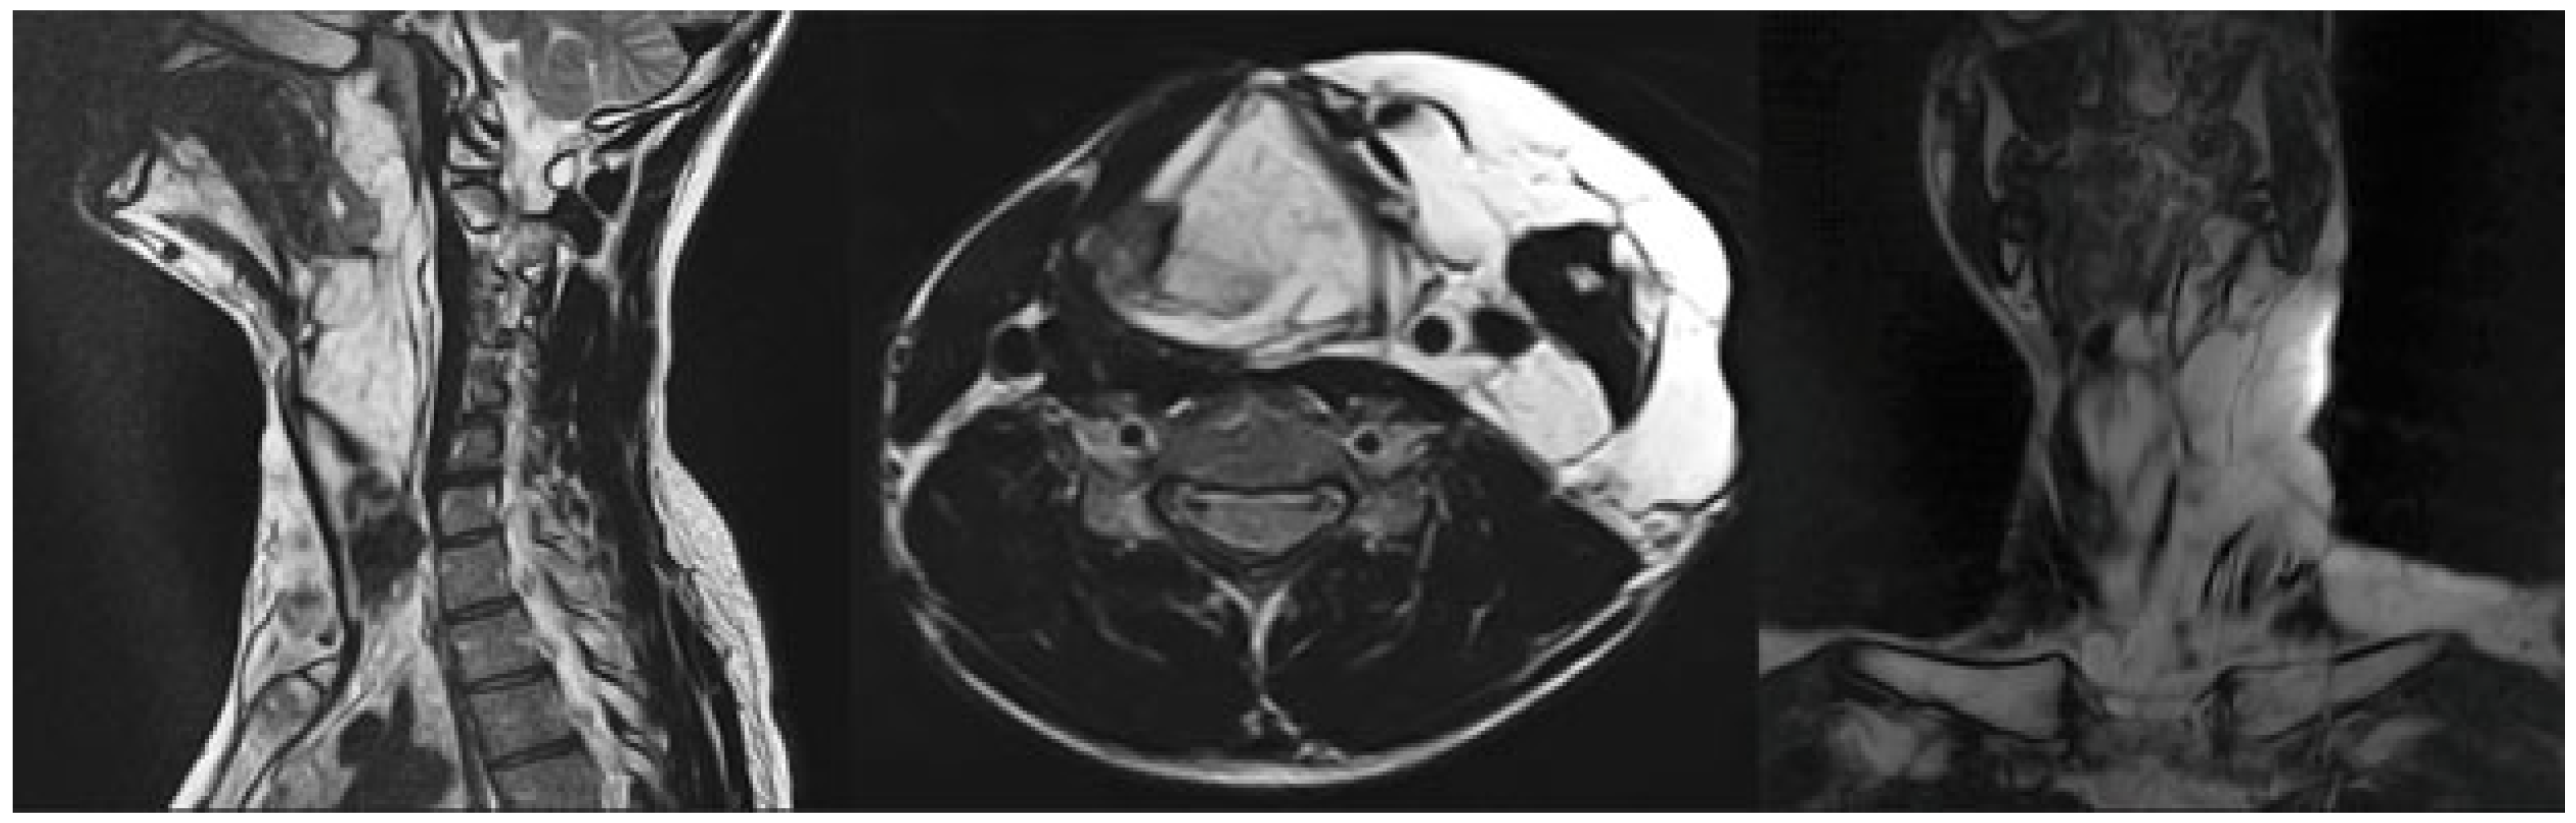

3.1. Magnetic Resonance Imaging (MRI) Findings

| 10 | M | 23 | Subglottic space, neck | 3 | 8217 | 3248 | Significant reduction (>50%) | None |